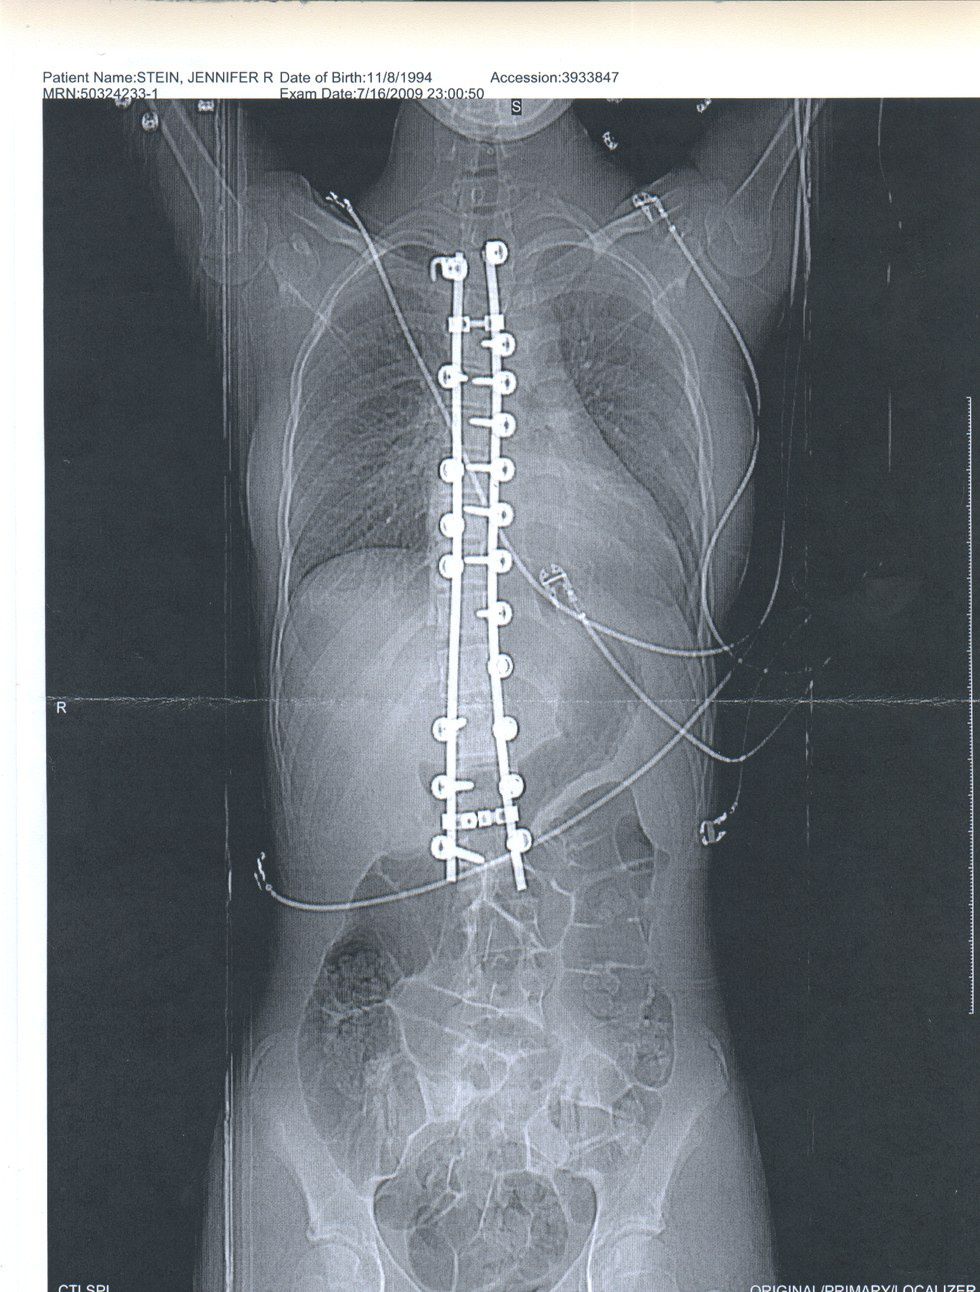

The scoliosis was painful, my body didn't function the way it used to. My muscles always ached and my ribs stabbing my lungs. I knew I wanted to have the surgery, and I decided right there that I wanted the surgery as soon as possible so I could play sport by my senior year of high school. The surgery consists of attaching titanium rods to my spine with surgical screws.

My time in the hospital was interesting. There was a lot of not sleeping that occurred, as I was checked on my a nurse every two hours. They needed to make sure I had enough meds, and to make sure I could still feel all of my limbs. The night the day after my surgery, I was whisked away to have a CAT scan, and the news we got back from the doctors was not good. They had put three of the screws in my lower vertebrae not the correct angle. I needed to have a second surgery. So on the 17th of July, I remember they disconnected me from my morphine drip and knocked me out for a second five hour surgery.